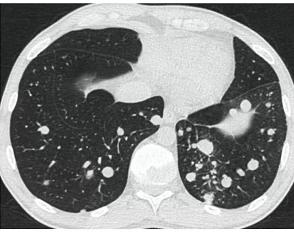

КТ имеет высокую чувствительность в выявлении изменений в легких, характерных для COVID-19. Применение КТ целесообразно для первичной оценки состояния ОГК у пациентов с тяжелыми прогрессирующими формами заболевания, а также для дифференциальной диагностики выявленных изменений и оценки динамики процесса. КТ позволяет выявить характерные изменения в легких у пациентов с COVID-19 еще до появления положительных лабораторных тестов на инфекцию с помощью МАНК. В то же время, КТ выявляет изменения легких у значительного числа пациентов с бессимптомной и легкой формами заболевания, которым не требуется госпитализация. Результаты КТ в этих случаях не влияют на тактику лечения и прогноз заболевания при наличии лабораторного подтверждения COVID-19. Поэтому массовое применение КТ для скрининга асимптомных и легких форм болезни не рекомендуется.

9. Оценка динамики течения выявленной пневмонии COVID-19 проводится по клиническим показаниям с применением следующих методов визуализации:

- оптимально: выполнение КТ исследования легких по стандартному протоколу без внутривенного контрастирования;

Комментарии. Кратность повторения КТ, РГ или УЗИ зависит от клинических показаний, диктующих необходимость оценки динамики. Рекомендуемая кратность повторения для КТ и РГ - не реже, чем один раз в 7 дней.

Объективная оценка динамики возможна только при сопоставлении данных одного вида исследования, например, КТ или РГ. Сравнение визуальной картины пневмонии при использовании различных методов визуализации затруднено и, как правило, субъективно. Возможно использование УЗИ легких, но только при условии наличия (1) первоначальной информации об истинном объеме и причине поражения легких и (2) подготовленного врачебного персонала.